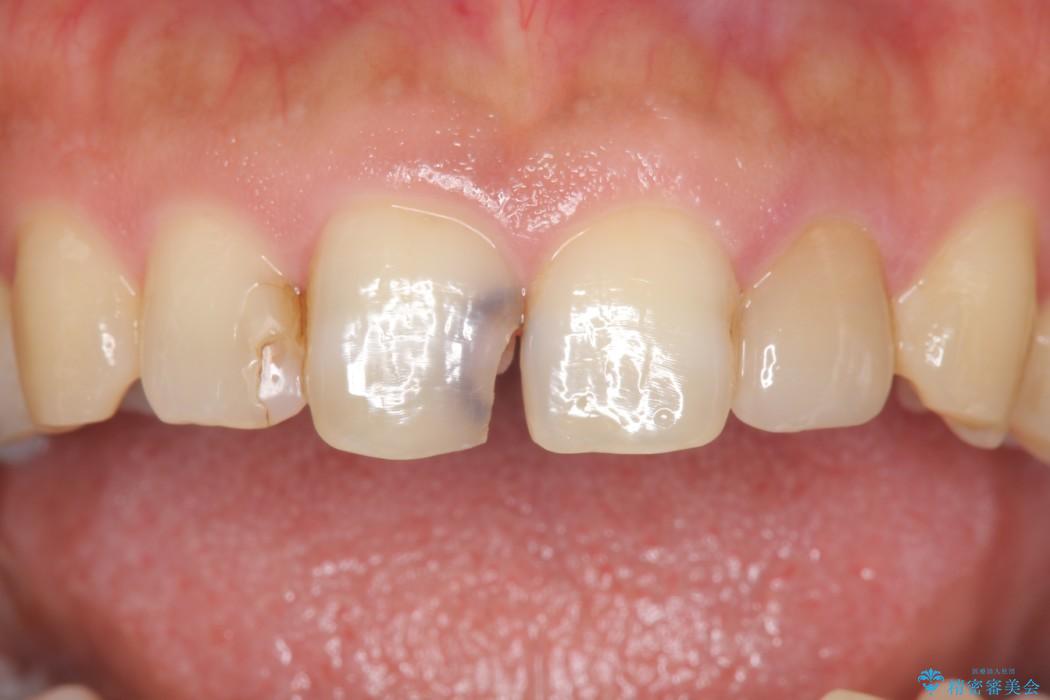

虫歯による歯の欠けと変色を主訴に来院されました。

神経に届く一歩手前の虫歯を前歯に認めました。

虫歯の範囲が大きいため詰め物ではなく、被せ物を使用した治療を行うこととしました。